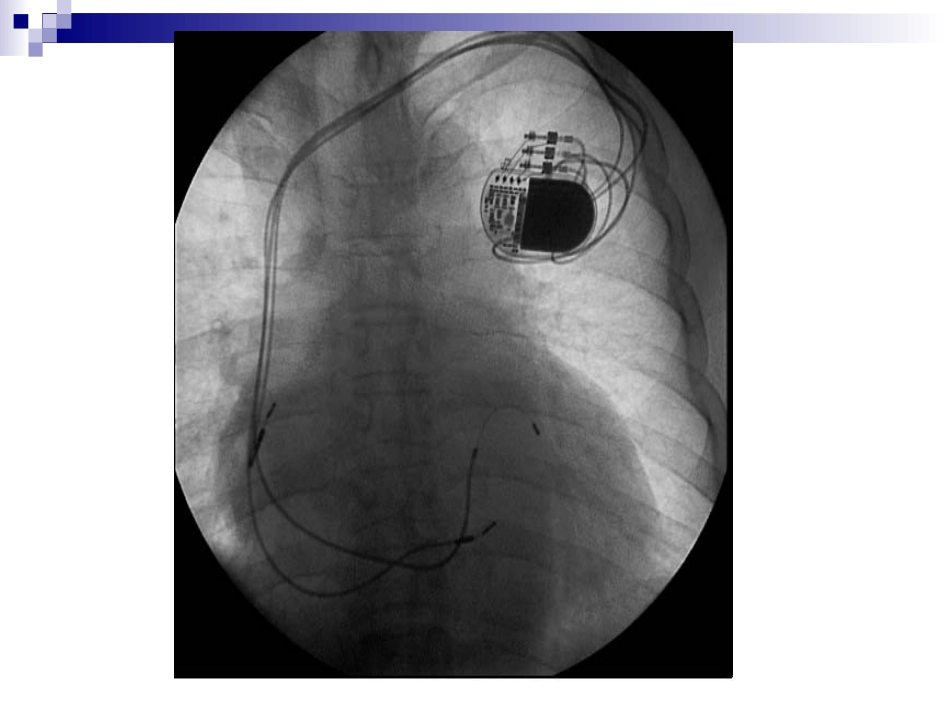

心脏起搏定义人工心脏起搏(artificialcardiacpacing)是通过人工心脏起搏器或程序刺激器发放人造的脉冲电流刺激心脏,以带动心脏搏动的治疗方法。主要用于治疗缓慢心律失常,也用于快速的心律失常和治疗。什么是心脏起搏器?心脏起搏器由脉冲发生器、导线和电极组成。脉冲发生器呈扁圆形,体积非常小,大约有40506毫米,重量约30克。它实际上是一个微型计算机,由高性能电池提供能量。起搏器通常埋植在上胸部的皮下,它的导线通过静脉到达心脏,导线顶端的电极固定在心脏的内侧面心肌上。起搏器工作时,脉冲发生器发出的电脉冲,经导线、电极传到心肌,心肌感受到电脉冲刺激产生收缩。同时,起搏器电极也将心脏的电活动收集起来存入脉冲发生器内的芯片内,以便进行分析。人工心脏起搏器工作原理:监测...